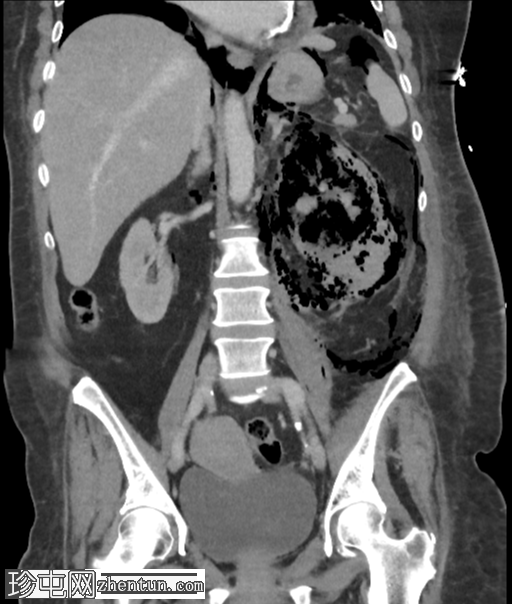

X线检查

纵隔气肿

腹膜后气肿

左肾区异常气体

底不张